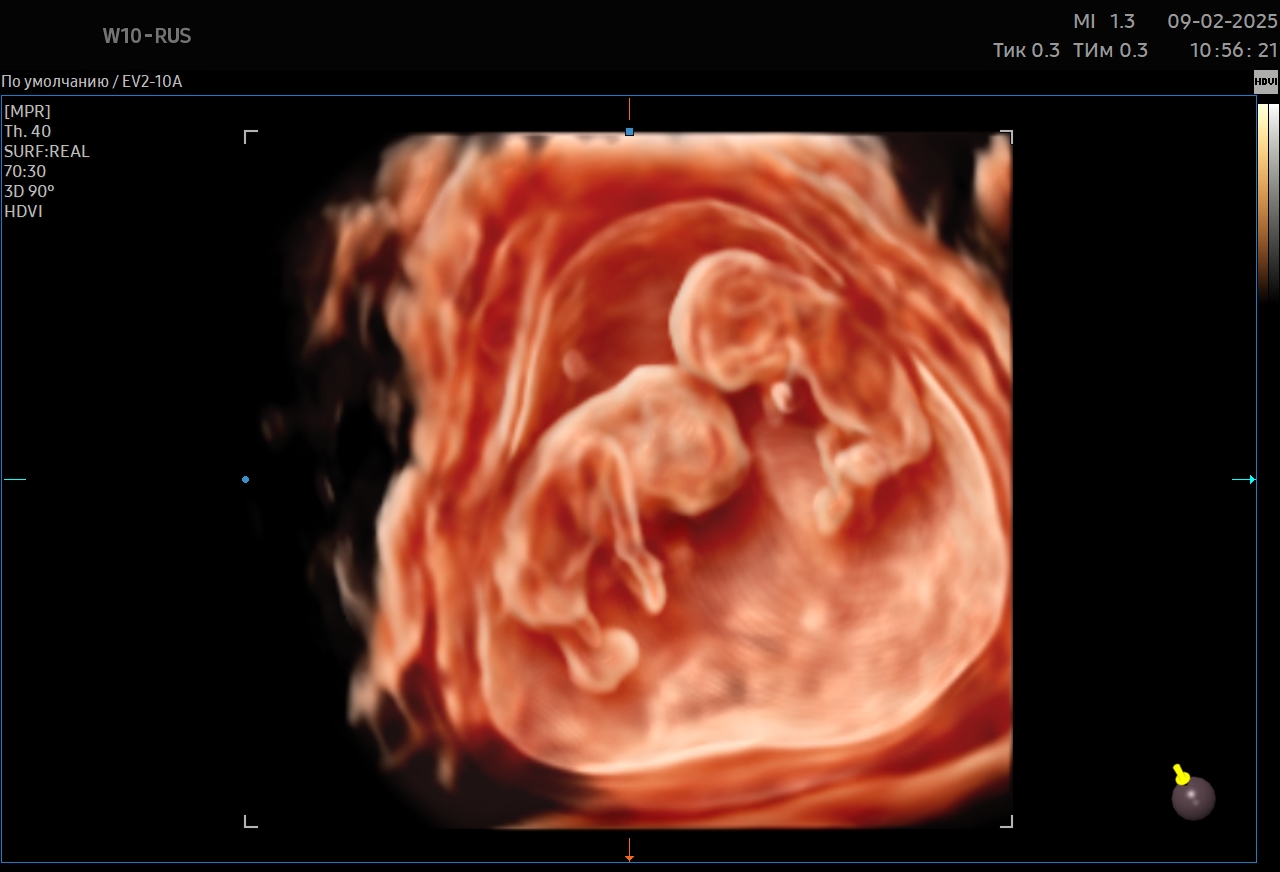

Ультразвуковое исследование – это наиболее информативный метод диагностики состояния плода и беременной женщины. В «Мать и дитя» оно проводится с помощью современного ультразвукового оборудования, которое формирует максимально детализированное изображение. УЗИ дает возможность обнаружить особенности развития малыша на самой ранней стадии. Метод абсолютно безопасен и может выполняться любое количество раз.